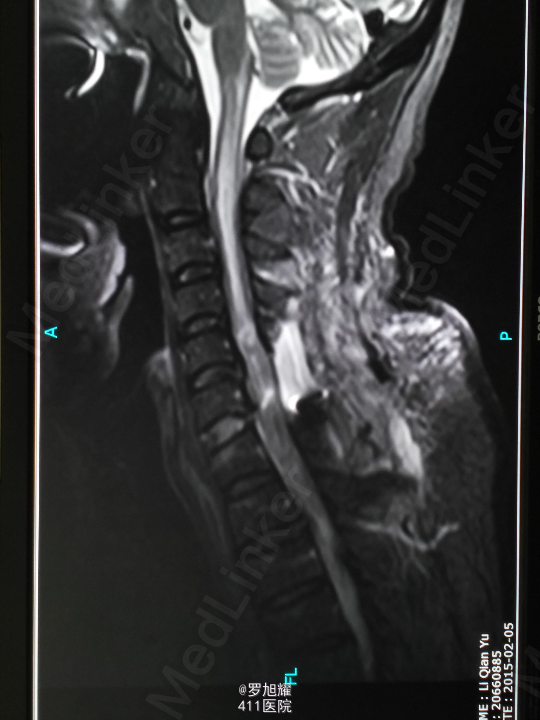

查体:双上肢前臂及以远感觉丧失,躯体自第二肋间平面以下感觉丧失。耸肩可,双侧三角肌、肱二三头肌肌力2级,腕关节屈伸、旋转及各指肌力0级。腱反射阴性,但球海绵体反射已经阳性。影像学检查示颈椎骨折脱位伴颈髓损伤。

诊断:颈6/7骨折脱位伴高位截瘫。处理:立即甲强龙冲击、脱水、保胃、营养神经治疗。首选治疗方案是颅骨牵引复位后前路融合固定,较后路稳定,出血也少,和家属谈话后开始颅骨牵引复位,4kg起步,每半小时增加1kg直至14kg,调整颈椎屈伸位,再加用手法牵引仍不能复位。改用备选方案,急诊行后路切开减压撬拨复位内固定,术后瘫痪症状部分改善。随访3月双上肢前臂及手部感觉恢复,仅双手掌尺侧及小指感觉障碍,双侧三角肌、肱二三头肌肌力4-5级,腕关节屈伸、旋转肌力左侧3级,右侧3-4级,但各指肌力仍0级。